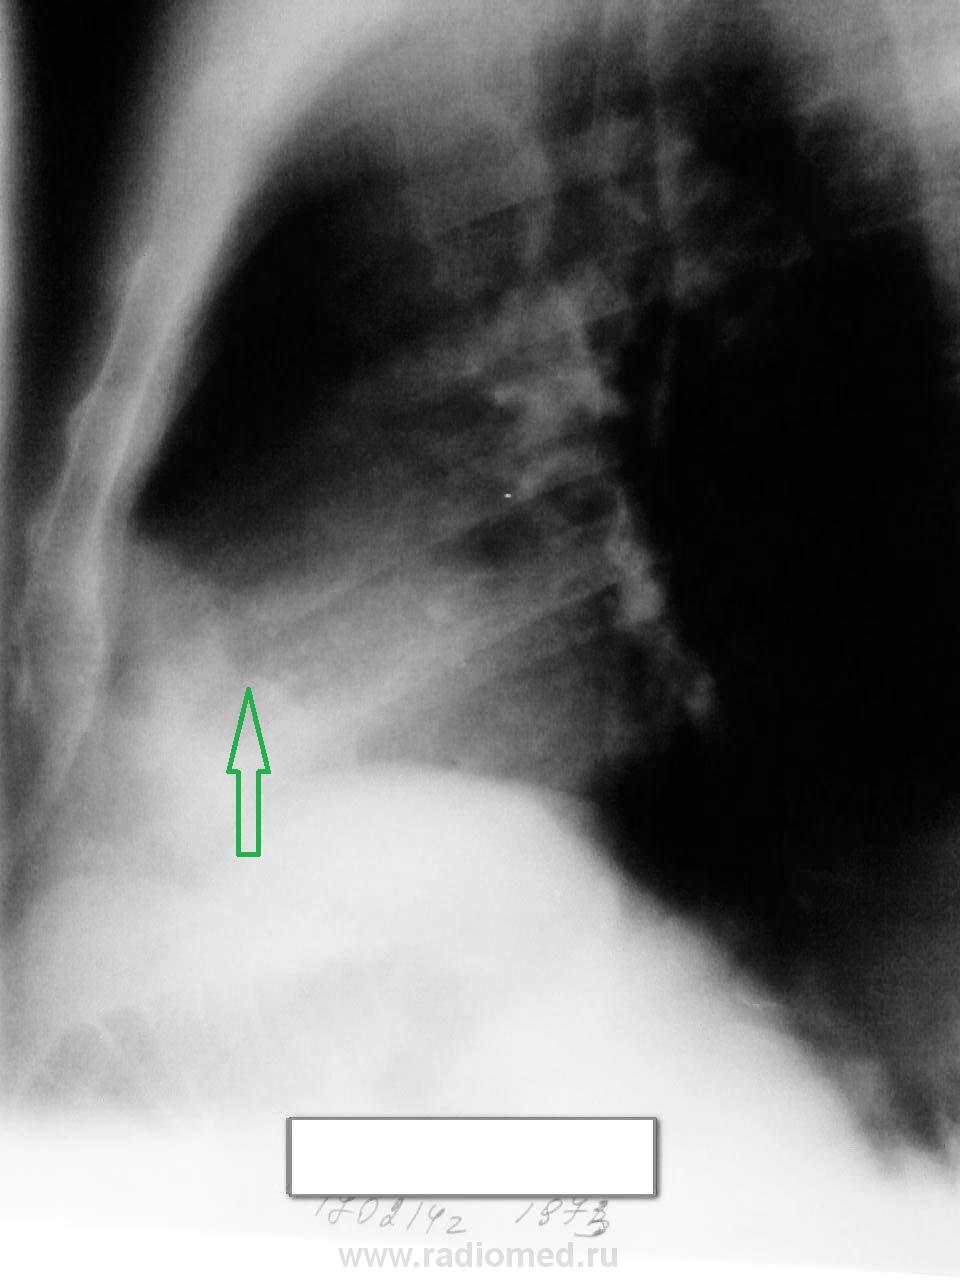

Мужчина 1973 г.р. Гиперстеник. Жалоб не предъявляет. Можно ли расценить затемнение в переднем кардиодиафрагмальном углу слева как абдоминомедиастинальную липому или есть ещё какие-нибудь варианты?( всегда это левый передний кардиодиафрагмальный угол вызывает затруднения!)

Вот снимкм.